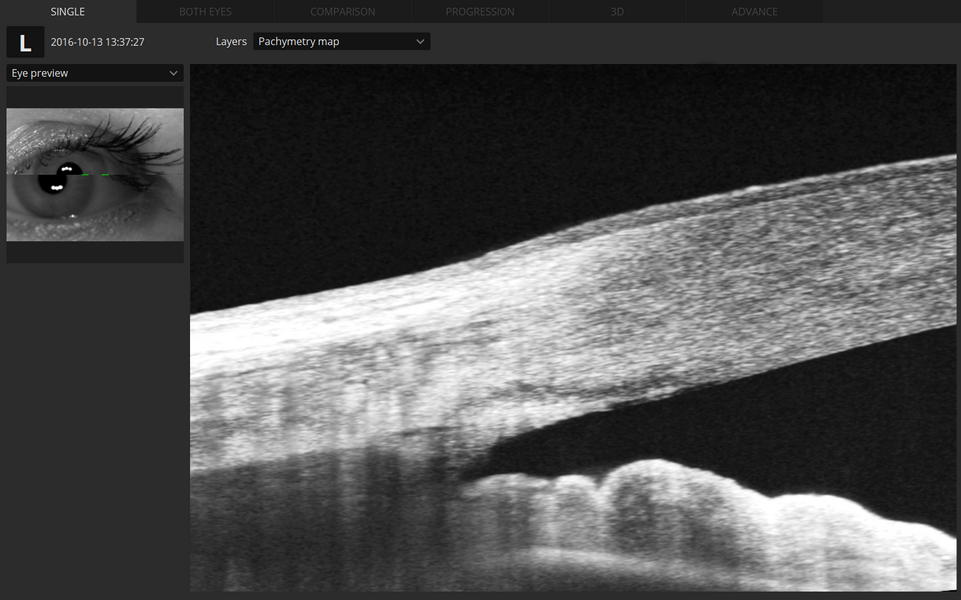

- Παχυμετρικός χάρτης του κερατοειδούς χρήσιμος στην προεγχειρητική εκτίμηση πριν από το Laser μυωπίας και στην πρώιμη διάγνωση παθήσεων όπως ο κερατόκωνος.

- Ποσοτική μέτρηση της γωνίας του προσθίου θαλάμου η οποία γίνεται χωρίς επαφή με τον οφθαλμό και αντικαθιστά τη δυσάρεστη για τον ασθενή εξέταση της γωνιοσκοπίας.

- Εκτίμηση των παθήσεων και των τραυμάτων του κερατοειδούς, του προσθίου θαλάμου και του φακού.